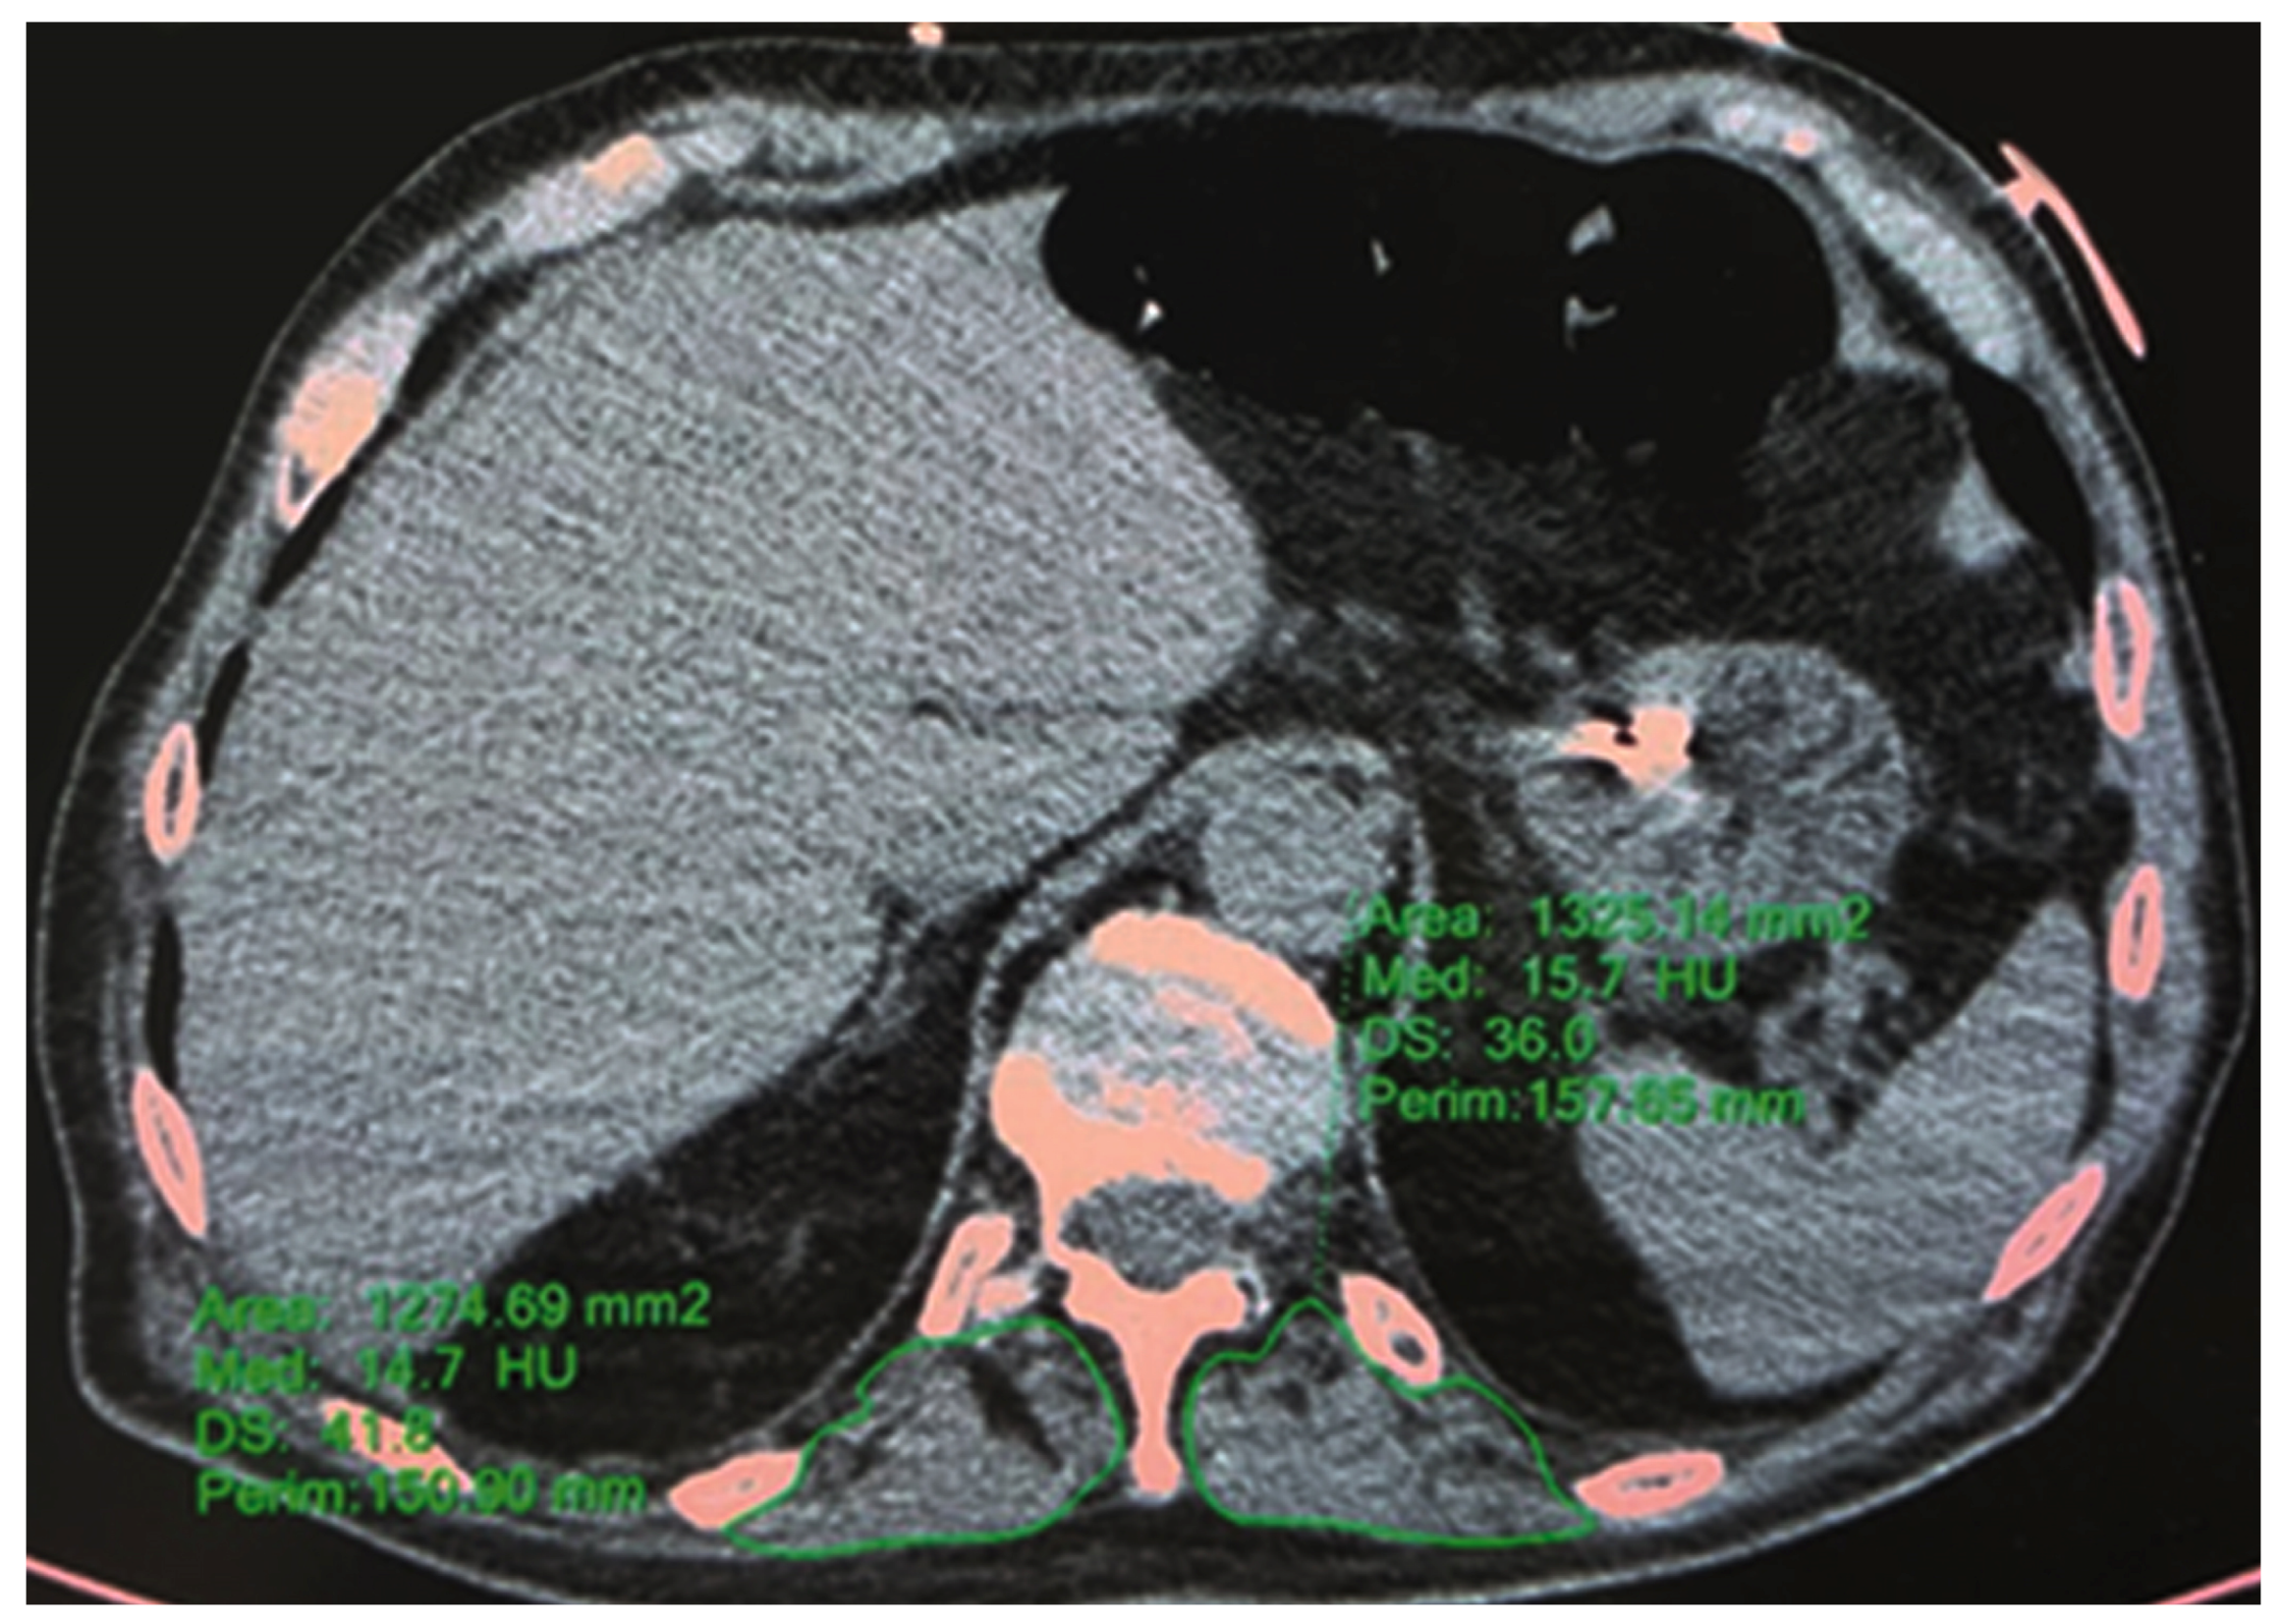

2.3.2. HRCT—T12 Paravertebral Muscle Area and Density

2.4. Statistical Analysis